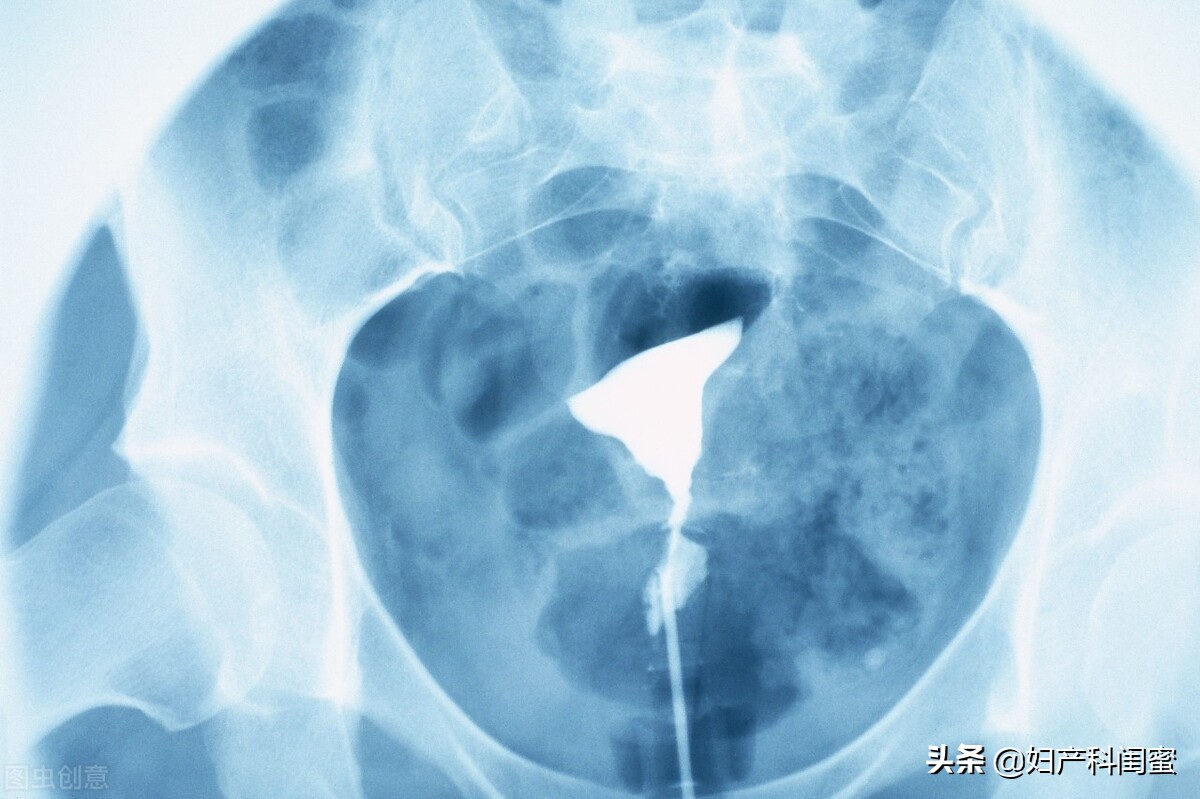

2、子宫输卵管造影检查 是检查子宫腔形态、输卵管通畅度的一线筛查手段,是将造影剂缓缓推注入子宫腔、输卵管内,后用X线对造影剂显影成像,判断成像是否有异常,粘连、阻塞、积水及其他异常情况,推注压力的高低判断阻塞程度——黏连、通而不畅、完全阻塞。X 线下子宫输卵管造影检查的应用非常广泛, 具有比较理想的可重复性,但是却可能出现碘过敏反应,逆流时有肺栓塞风险,而且存在放射性,除此之外患者在检查后近期不适合怀孕。